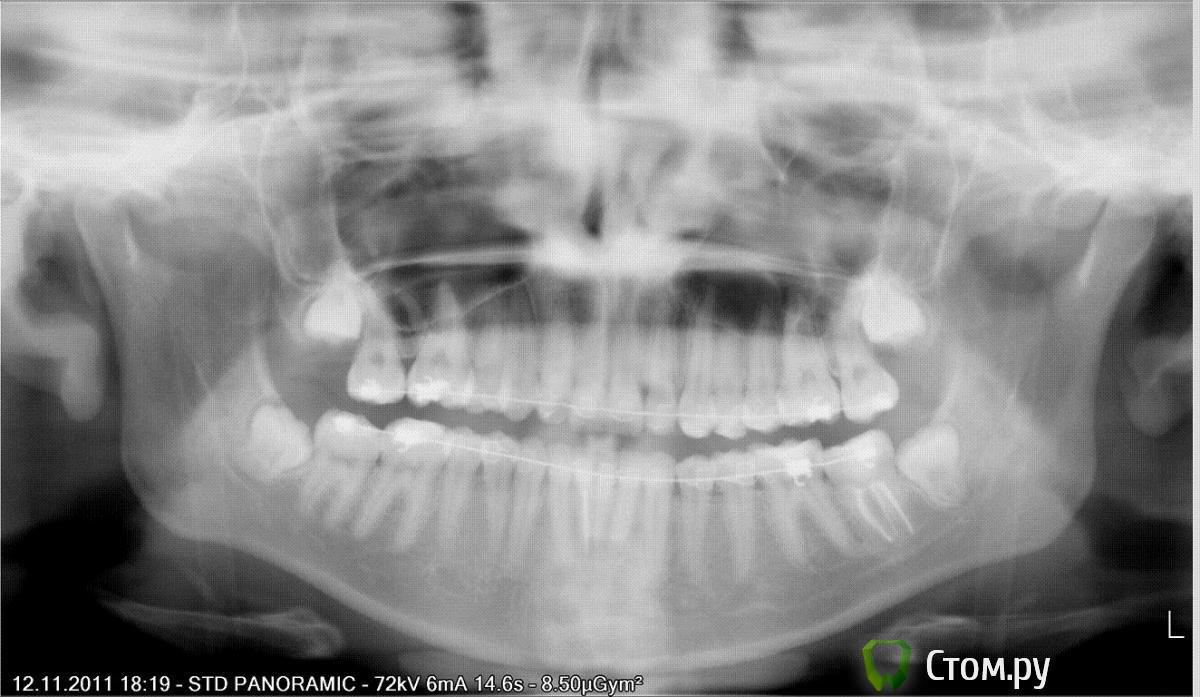

Alerta Опубликовано 12 ноября, 2011 Поделиться Опубликовано 12 ноября, 2011 Уважаемые ортодонты и разбирающиеся в деле люди, прошу вас посоветовать, что можно сделать в моей ситуации. С правой стороны на верхней челюсти пятерка росла на небе, перед постановкой брекетов ее хотели задвинуть в зубной ряд, но при попытке вылечить кариес, оказалось, что она не подлежит восстановлению и проще ее удалить и подвинуть на ее место 6 и 7. Вот, собственно, и все, что можно сказать мне 21 год, в брекетах уже 2 года. Мой ортодонт готов к снятию через 2-3 месяца и говорит, что сделал все возможное. Меня совершенно не устраивает результат. Та причина, по которой я поставила брекеты так и осталась.А именно - это перекос, по всей видимости из-за той злополучной пятерки. Хочется получить ровные зубки хотя бы в зоне улыбки.Помогите, кто чем может Ссылка на комментарий

Skip Опубликовано 12 ноября, 2011 Поделиться Опубликовано 12 ноября, 2011 Та причина, и все, что можно сказать по которой я поставила брекеты так и осталась.А именно - это перекос, по всей видимости из-за той злополучной пятерки. Хочется получить ровные зубки хотя бы в зоне улыбки.Помогите, кто чем можетА чем Вам помочь? Здесь "перекошена" верхняя челюсть целиком и причина не в 5-ке. Исправить этот перекос нехирургически довольно просто, но это особый разговор.И ещё к Вам вопрос, как Вы себя чувствуете после стягивания зубов, нет ли головных болей и пр.? Ссылка на комментарий

Alerta Опубликовано 14 ноября, 2011 Автор Поделиться Опубликовано 14 ноября, 2011 (изменено) По мне так перекошена верхняя и нижняя челюсть вместе. На консультации 2 других ортодонта сказали, что это из-за уплощения со стороны удаленной пятерки. А чувствую я себя прекрасно, никаких болей и прочего, в общем брекеты и все, что с ними связано никак не сказались на моем самочувствии.Хиррургическое исправление не рассматриваю в принципе, там просто нечего исправлять хиррургически. Думаю, что пока мне не сняли брекеты, все исправимо. Другое дело, что у меня стоят сапфировые, и один из ортодонтов сказал, что из них больше ничего не выжмешь, они не позволяют.Хочется узнать, что именно тут нужно делать. Один доктор предложил все исправлять микроимплантами. По его мнению их нужно 3-4 штуки. И это еще 6-8 месяцев лечения и дополнительные затраты. Хотелось бы долечиться у своего врача, но она говорит, что не видит перекос и добилась максимально возможного по ортодонтии и эстетике.Можно ли все исправить эластиками, гнутыми дугами и микроимплантами, расскажите поподробней, пожалуйста. Изменено 14 ноября, 2011 пользователем Alerta Ссылка на комментарий

Премоляр Опубликовано 14 ноября, 2011 Поделиться Опубликовано 14 ноября, 2011 Ну,доктор всетаки помог вам...Ситуация улучшилась. Разумеется,отсутствие 5ки и мезиал.смещение 6 и 7 сказались на симметрии.Но это ЕСТЕСТВЕННО при одностороннем удалении. "Перекос" в.ч. возможно был связан с длительным несимметричным жеванием(из-за смещения зубов вследствие небного положения 5ки) с превалированием на "здоровой" стороне.Чисто механически это решаемо...Врач решает для себя сам,какой техникой ему это испраить-изгибами на дугах,с использованием микроимплантов,многопетлевой техникой и т.д...Возможно целесообразнее было для коррекции "перекоса" раскрыть место под имплантацию в обл.5киП.С. Я предположил это,основываясь на представленной инфе,кот.мне недостаточно. Не вижу соотношение жеват.зубов справа и слева Ссылка на комментарий